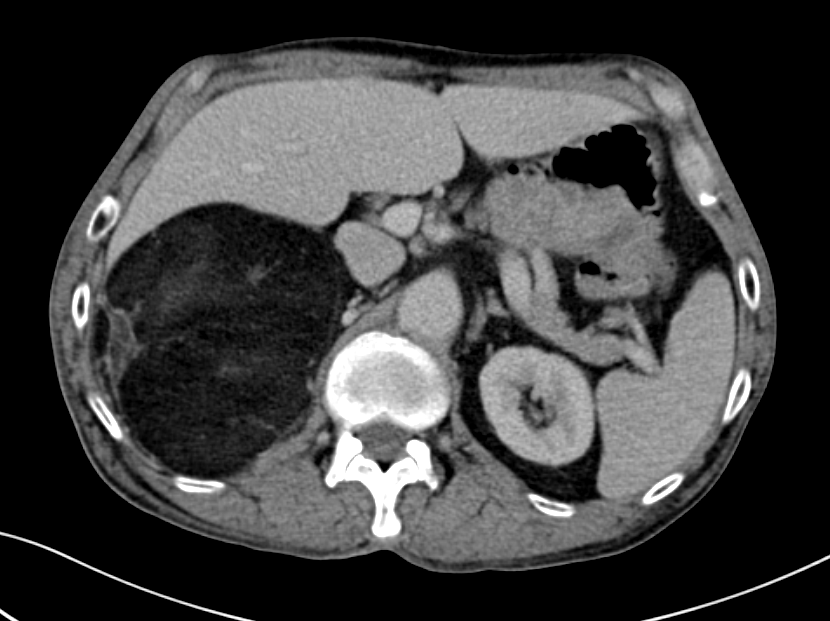

腹部CT:右肾上腺巨大肿瘤

蔡志康联合呼吸科、麻醉科制定了缜密的手术方案,对每一步潜在的风险都做好了预案。手术当天,在打开彭老的腹腔后,只见硕大的肿瘤几乎霸占了右侧腹腔一半的空间。在分离肾脏时,发现肿瘤包膜与肾包膜粘连严重,在评估肾脏完好后,用超声刀将界限一点点游离开来。就这样一点点地攻克每一个难点,肿瘤终于被完整地切除了下来。经测量,肿瘤的最大径达到了20cm。